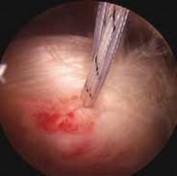

2. Long head of biceps tendinopathy encompasses a spectrum of pathology, including intratendinous signal change, synovitis of the sheath, partial tearing, and frank tendon rupture (

FIG 2

).

FIG 2 • Arthroscopic images of tendinopathy and tearing of the long head of the biceps tendon. NATURAL HISTORY 8. Little is known about the natural history of biceps tendinopathy, so prediction of a patient’s clinical course is difficult.